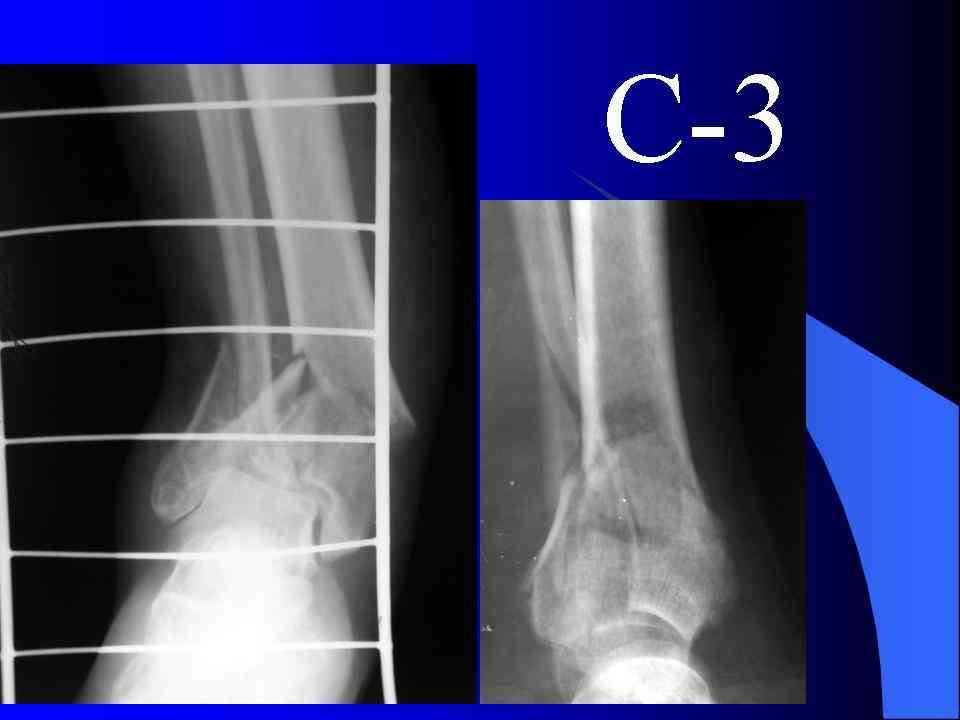

На рентгенограммах типичный перелом пилона по типу С-3. есть опыт до 100 открытых опреаций у нас в клинике. 20 примерно в год. Принцип один -все внутрисуставные переломы нуждаются в открытой репозиции и внутренней стабильной фиксации. При поступлении КТ не надо, так как получается только нагромождение костей. Истинной картины нет. Главное восстановить длину малоберцовой кости - это ключ к успеху. При поступлении меньше всего надо думать о сосудистых расстройствах, т.к. сама операция и репозиция даже сначала частичная даёт улучшение сосудитых нарушений. Причём очень быстро. Операция в 2этапа. При поступлении доступ позади наружной лодыжки, причём обязательно. После этого репозиция малоберцовой кости и фиксация пластиной 1/3 трубки под винт 3,5. Дренаж и любой аппарат наружной фиксации. Затем после спадения отёка на 5-7-10 день аппрат снимается и дугообразный разрез спереди от медиальной лодыжки 10-12 см. Главной чтобы расстояние между 1 и вторым разрезом было не меньше 7-8 см. Тогда не будет некрозов лоскутов. Таранная кость используется как матрица на неё укладываются отломки и фиксируются пицами. Ренг-контроль. Отломки лежат все отдельно, но ничего не высыпется. При переломах С-3 всегда нужна костная пластика (из крыла). Фиксация пластиной лист клевера простой или LCP. Гипс не нужен. Дренаж до 48 часов. Операция длится 3-4 часа обязательно без жгута. Посылаю примерно такой же случай.

Посылаю результат лечения предыдущего больного через год.